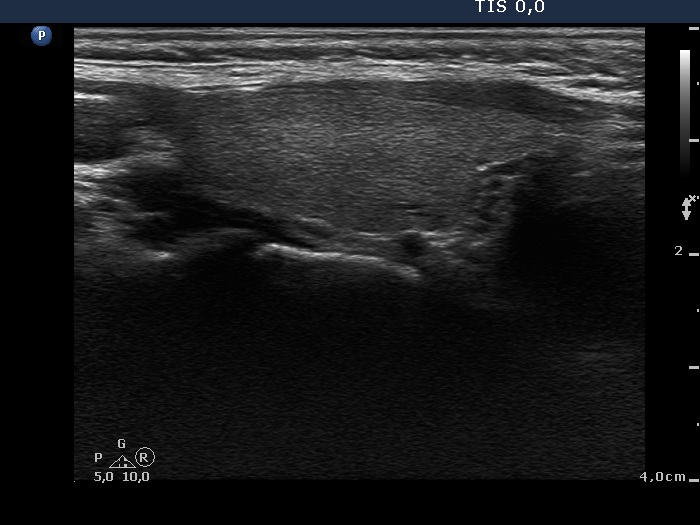

Two years after the initial examination (ultrasonographic picture 3)

Right lobe, longitudinal view.